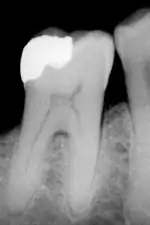

The large amount of mineral in enamel accounts not only for its strength but also for its brittleness.[6] Tooth enamel ranks 5 on Mohs hardness scale (between steel and titanium) and has a Young's modulus of 83 GPa.[4] Dentin, less mineralized and less brittle, 3–4 in hardness, compensates for enamel and is necessary as a support.[7] On radiographs, the differences in the mineralization of different portions of the tooth and surrounding periodontium can be noted; enamel appears lighter than dentin or pulp since it is denser than both and more radiopaque.[8]